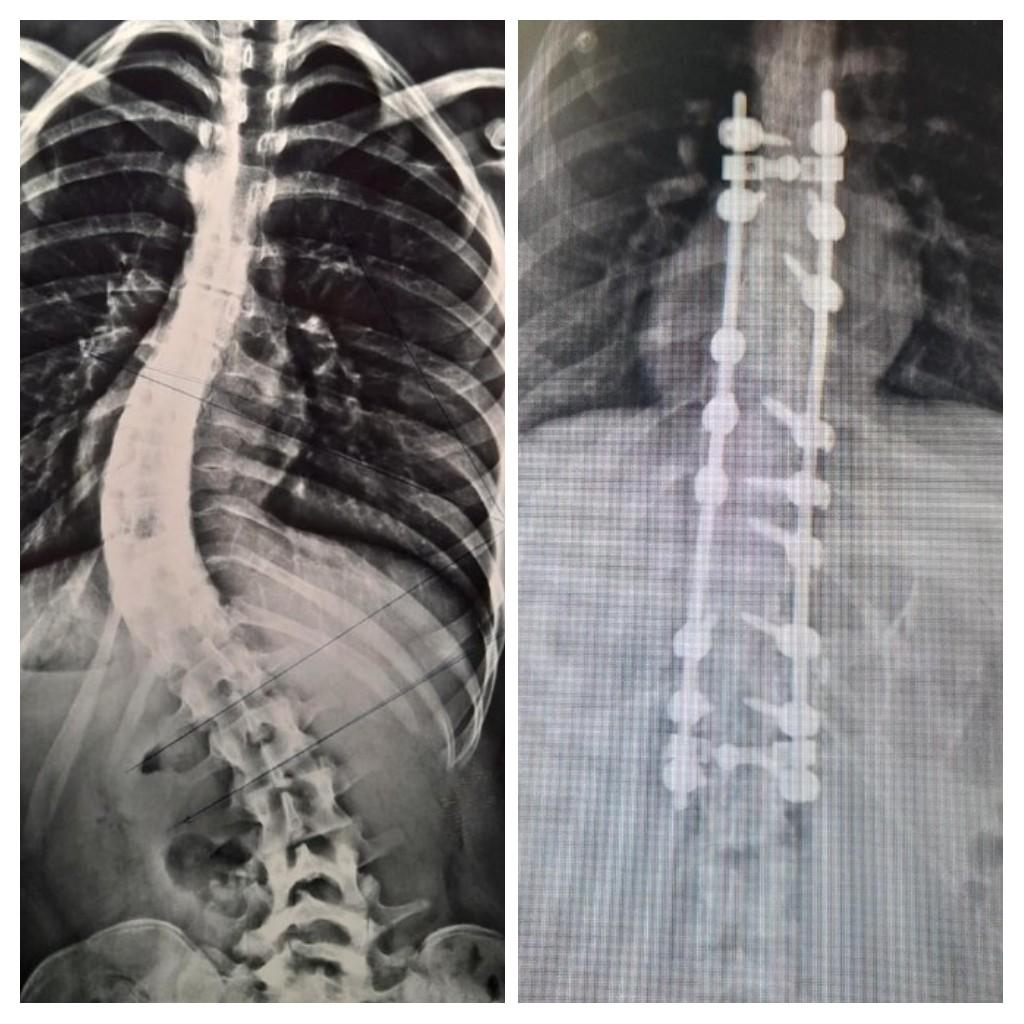

En el Hospital Interzonal San Juan Bautista, de manera exitosa, se realizó días atrás una nueva cirugía para corrección de columna vertebral en una joven paciente que presentaba escoliosis dorsolumbar grave

En un abordaje integral y colaborativo entre los hospitales San Juan Bautista y el de Niños Eva Perón, un especializado equipo traumatológico, dio intervención a una paciente de 17 años con malformación congénita, que había iniciado su tratamiento en el nosocomio infantil y que finalmente pudo ser operada en el de atención adulta.

En la Cirugía, que tuvo una duración de más de 4 horas de quirófano, se logró la reducción de la deformación dorsolumbar mediante la colocación de barras y tornillos pediculares. Los Traumatólogos que estuvieron a cargo fueron Nicolás Flores Kanter y Pablo Ovejero -este último en colaboración por parte del Hospital de Niños-; con la anestesista, Dra. Adriana Bustos, y los instrumentadores Aldo Espilocin y Claudia Sánchez.